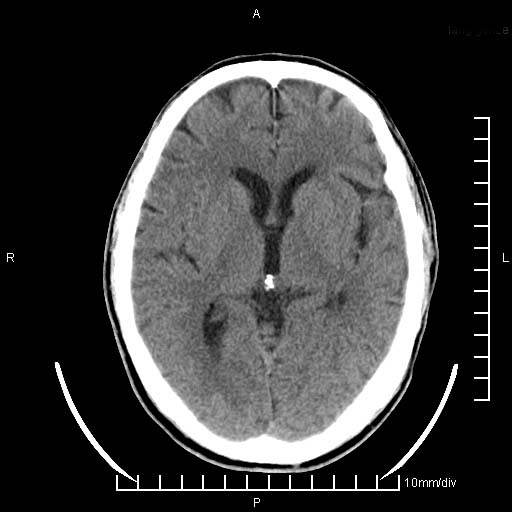

临床以双下肢浮肿,疼痛收治,无明显神经系统症状,既往无梗塞,出血病史。左颞叶见低密度灶,考虑什么?

考虑左侧颞叶脑软化灶。

无强化 无占位 软化灶吧

无强化、 无占位、局部脑沟增宽, 软化灶吧。